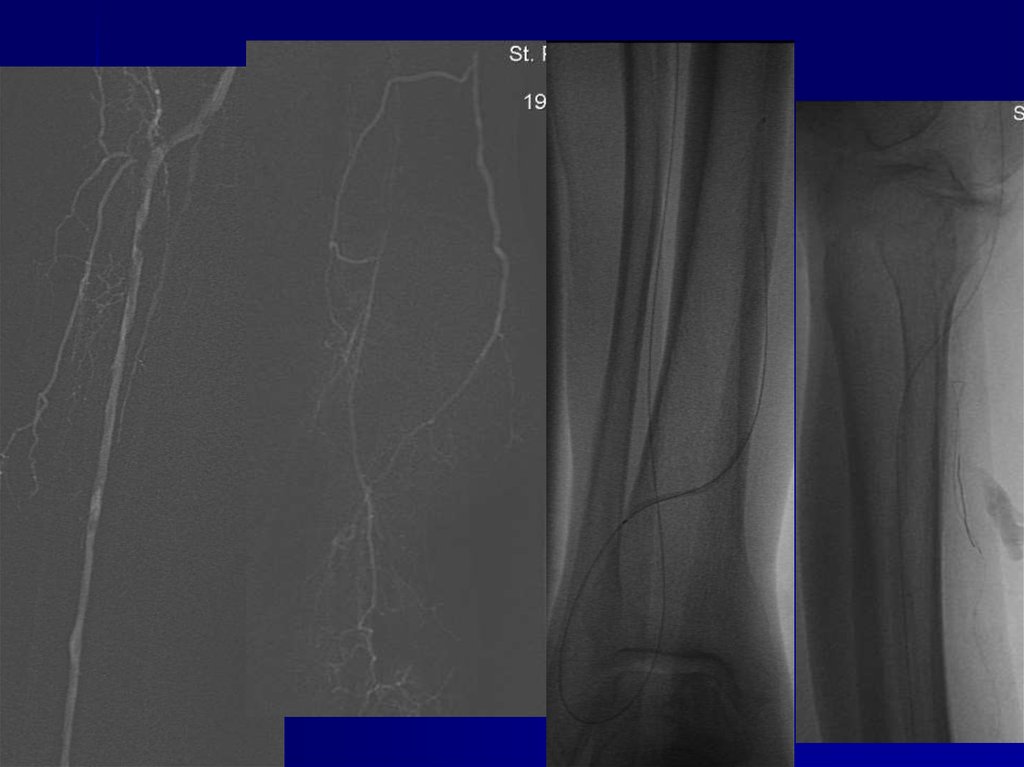

ПЕРЕХОДНЫЕ ВАРИАНТЫ МЕЖДУ НОРМАЛЬНЫМ И

ИЗМЕНЕННЫМ ДИСТАЛЬНЫМ КРОВОСНАБЖЕНИЕМ